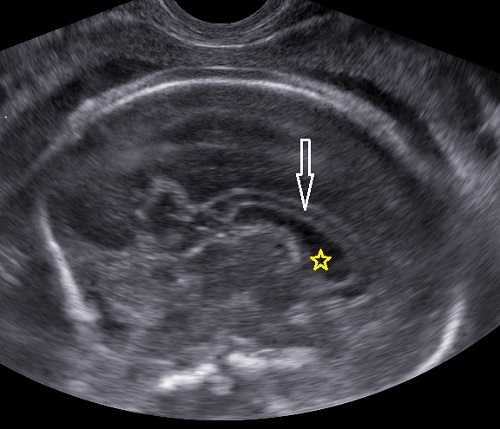

Cuerpo calloso: es una estructura compuesta por haces nerviosos cuya función es la de conectar e integrar regiones corticales homólogas entre ambos hemisferios cerebrales. Su ausencia total puede conducir a problemas cognitivos y del desorrollo psicomotriz o pasar totalmente desapercibida. Su ausencia parcial, paradójicamente, se asocia con peor pronóstico. Como estructura ecográfica, es una de las más bellas que hay en el cerebro pero, para obtenerla se requiere pericia y muy buena resolución ecográfica. Sus alteraciones congénitas son diagnóstico de problemas primarios del desarrollo cerebral y se manifiestan con cambios indirectos en otras secciones cerebrales, especialmente ventriculomegalia.

Las estructuras intracraneales después de la semana 18-20 del embarazo son muy características y permanecen visualmente invariables hasta el final del embarazo, solo modificando sus tamaños a medida que el feto crece. Esto es de gran ayuda ya que permite determinar la aparición de cambios que podrían sugerir desviación de la normalidad y aparición de una malformación congénita o lesión adquirida por eventos externos especialmente relacionados a infecciones y accidentes vasculares fetales.